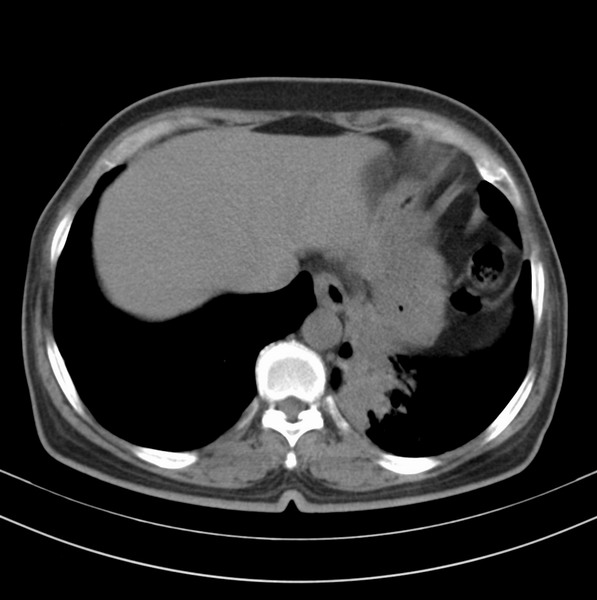

标题: CT20053:胸部增强请会诊。

女、63

咳嗽、胸痛四个月

包绕左下肺基底段的不规则的软组织肿块,段支气管腔变形、狭窄及阻塞性炎症,病变区不规则强化,又是老年女性支持楼上看法。

典型病例:左下肺基底段中央型肺癌,相应支气管狭窄并阻塞性炎症